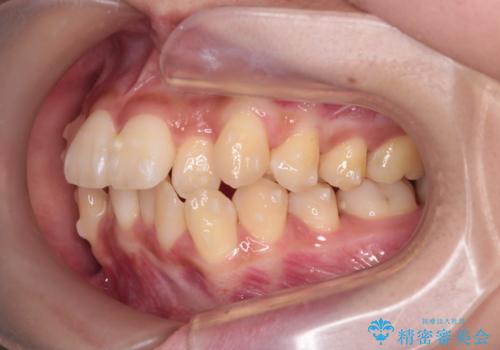

反対咬合を治したい。インビザライン

- 前歯の反対咬合を治したいことを主訴に来院されました。

インビザラインにて臼歯の遠心移動を行いながら、スペースを作り反対咬合を改善することができました。